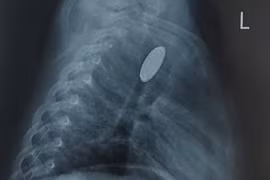

Chơi đùa, bé trai 5 tuổi vô tình nuốt phải đồng xu vào thực quản

Phụ huynh có con nhỏ không nên để trẻ chơi các món đồ chơi có kích thước nhỏ. Không để trẻ tiếp xúc với những đồ chơi nguy hiểm.